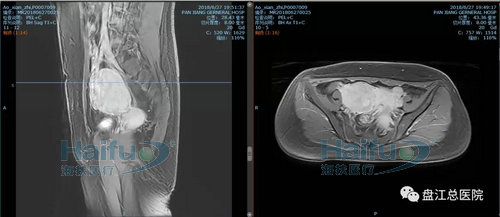

我院案例1:患者敖XX,44岁,多发性子宫肌瘤患者。

因经期延长1+月,发现盆腔包块12+天入院。患者于2018-6-29在我院行高强度聚焦超声消融治疗(HIFU)。在镇静镇痛状态下,治疗过程中未诉有特殊不适,安静休息。本次治疗时间70min。

术前后壁及右侧壁肌瘤增强,见病灶明显强化

术后后壁及右侧壁肌瘤增强,见病灶内已无强化,病灶发生凝固性坏死